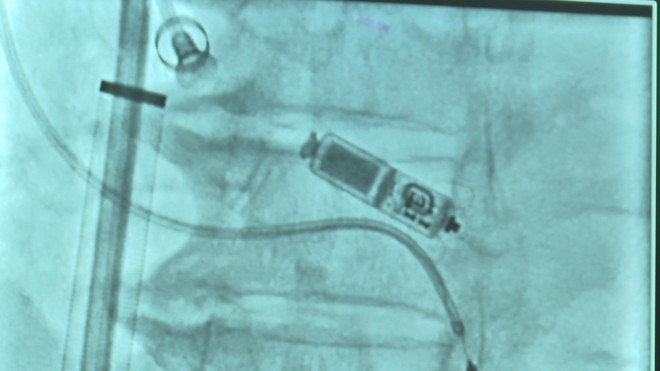

Trước tình thế cấp bách, ê-kíp bác sĩ đã chỉ định phương pháp đặt máy tạo nhịp tim không dây hai buồng. Thiết bị này chỉ nặng khoảng 2g, kích thước nhỏ bằng viên thuốc con nhộng, được đưa trực tiếp vào buồng tim thông qua ống thông từ tĩnh mạch đùi.

Đội ngũ bác sĩ tiến hành đặt máy tạo nhịp không dây cho bệnh nhân

Ca can thiệp diễn ra thành công tốt đẹp. Ngay sau đó, nhịp tim bệnh nhân đã ổn định ở mức khoảng 60 nhịp/phút, các triệu chứng mệt mỏi, choáng váng hoàn toàn biến mất. Bệnh nhân tỉnh táo, có thể vận động nhẹ ngay trong ngày đầu tiên và được xuất viện chỉ sau vài ngày theo dõi.